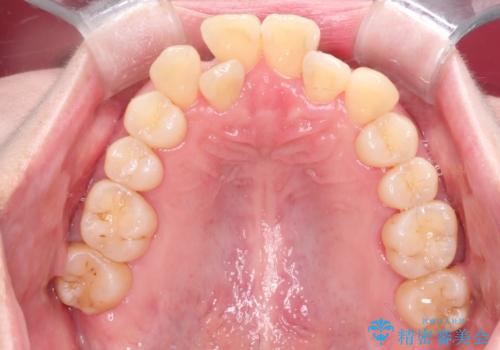

【インビザライン】ずれた前歯の噛み合わせをなおしたい

- 前歯の噛み合わせが悪いことを主訴に来院されました。

歯周病も併発していたため、歯牙への負担が少なくなるように治療計画をたて、インビザラインにて治療を完了しました。

矯正開始前に半年間、歯周治療を行ってからインビザラインを装着しています。